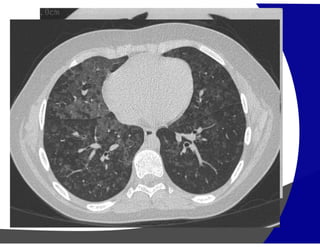

PADRÃO DE REDUÇÃO DE ATENUAÇÃO

“Manchas pretas”

Parasseptal

Centrolobular Panlobular

Enfisema Pulmonar